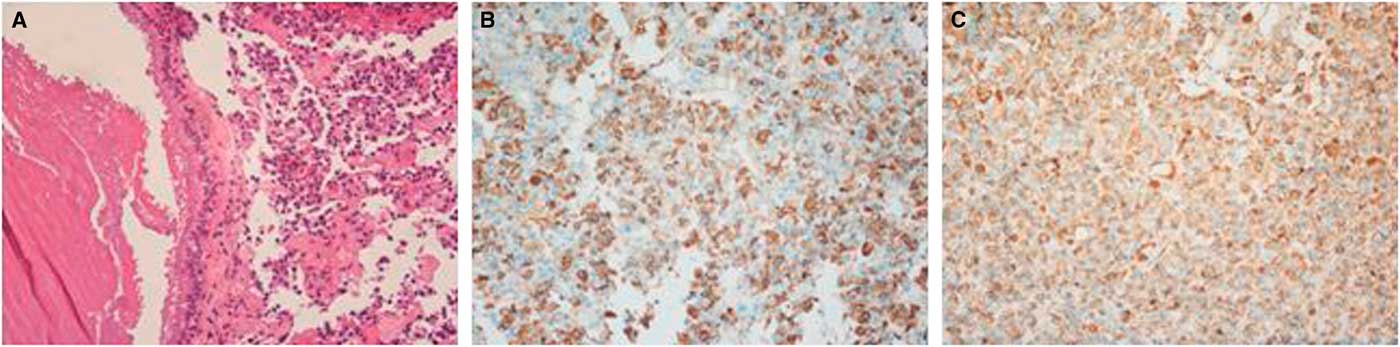

Microscopically, the tumor contained two components. The first component was monomorphic cells with round or oval nuclei containing stippled chromatin. The second component showed fragments of a cyst wall lined by simple cuboidal or pseudostratified ciliated columnar epithelium; the lumen of the cyst contained an abundance of myxoid materials (Figure 3A). Immunohistochemical analysis demonstrated positive results for PRL and GH/PRL in three patients (Figure 3B-C). A positive result for GH staining was indicated in one patient. There was no obvious staining in the other five cases, which were diagnosed as nonfunctional PAs (NFPAs) associated with RCC. Additionally, positive expression of cytokeratin in 8/18 cases was observed.

Figure 3 Hematoxylin-eosin and immunohistochemical findings for case 12. (A) Clusters of uniform PA cells with mucin-filled cyst. The cyst was lined by ciliated columnar epithelium (×200). (B) Immunostaining of GH was positive in the adenoma cells (×200). (C) PRL staining of adenoma cells showed strong reactivity (×200).